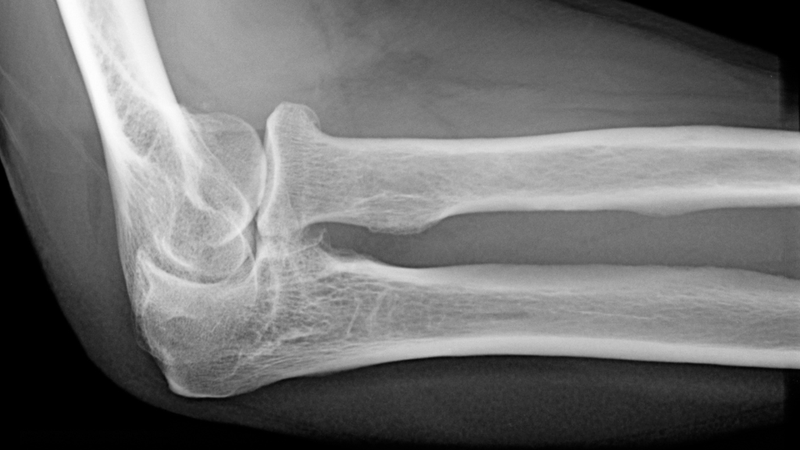

X quang khớp khuỷu là một phương pháp chẩn đoán hình ảnh quan trọng trong y khoa, giúp phát hiện sớm các vấn đề về khớp khuỷu như viêm khớp, gãy xương, hay tổn thương mô mềm. Phương pháp này không chỉ hỗ trợ bác sĩ trong việc xác định chính xác tình trạng bệnh lý mà còn góp phần xây dựng phác đồ điều trị hiệu quả. Đây là một công cụ không thể thiếu trong việc bảo vệ sức khỏe và nâng cao chất lượng sống của bệnh nhân.

X quang khớp khuỷu là một phương pháp chẩn đoán hình ảnh quan trọng trong y khoa, được sử dụng rộng rãi để xác định các bệnh lý liên quan đến khớp khuỷu. Qua hình ảnh X quang, bác sĩ có thể dễ dàng phát hiện các tình trạng như gãy xương, nứt xương, lệch trục, từ đó có cơ sở chính xác để đưa ra quyết định điều trị.

Gãy xương, một bệnh lý phổ biến và gây đau đớn, thường gặp do tai nạn hoặc hoạt động thể thao, có thể được chẩn đoán sớm nhờ vào hình ảnh X quang chi tiết, giúp ngăn chặn sự tiến triển của bệnh và bảo vệ chức năng khớp khuỷu, từ đó hỗ trợ bác sĩ trong việc lựa chọn phương pháp điều trị thích hợp như bó bột hay phẫu thuật.

Độ rõ nét của hình ảnh X quang hiện đại là yếu tố then chốt giúp xác định chính xác vị trí và mức độ của các bệnh lý như gãy xương, viêm khớp hay các tổn thương khác. Điều này không chỉ giúp đưa ra chẩn đoán nhanh chóng mà còn giảm thiểu khả năng sai sót trong quá trình đánh giá tình trạng bệnh, từ đó đưa ra phương pháp điều trị hiệu quả và phù hợp nhất cho bệnh nhân.